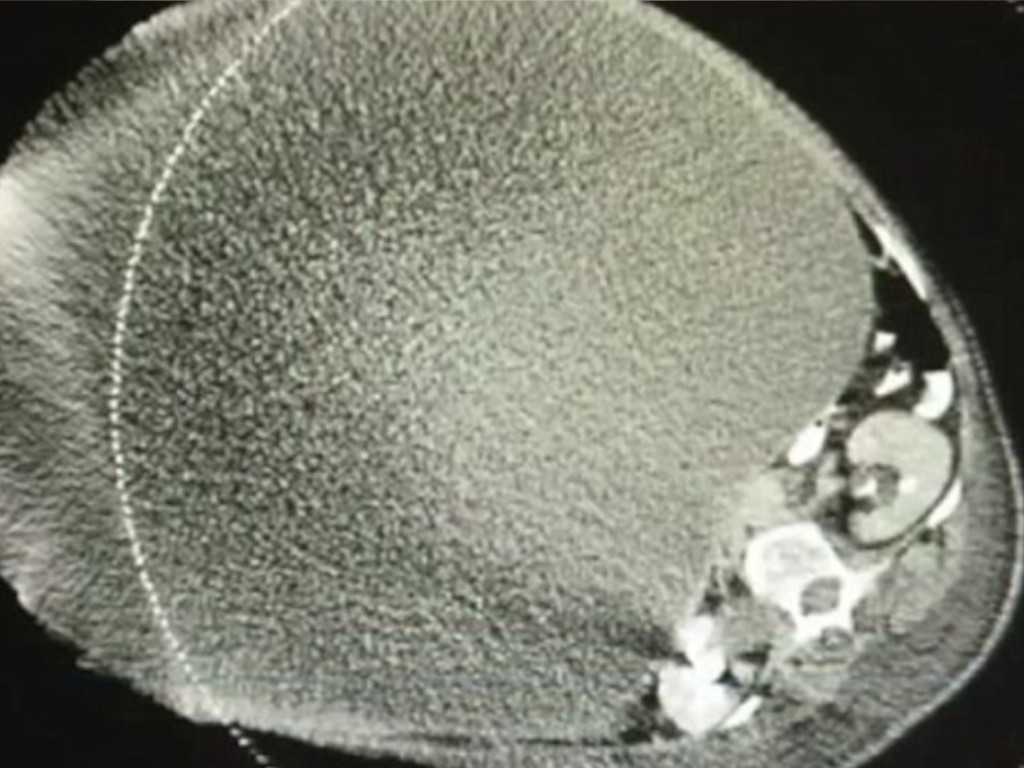

The CT scan showed that the growth inside her stomach was an ovarian cyst that was 24 centimeters thick and filled with fluid. In this case, it might have been blocking the blood flow to the ovaries and if it burst, it would put her life in danger.